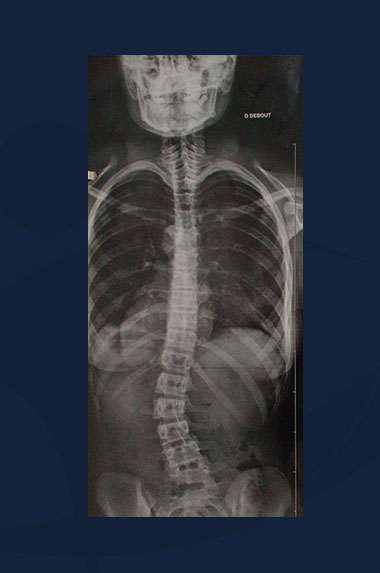

Lynda Smith

Clichés radiologiques du rachis (sans corset).

Scoliose Thoracique